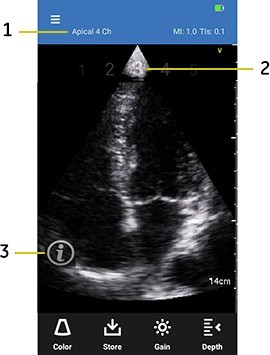

5. The live scan screen displays the following interface elements for the current protocol:

Interface elements

1. Current step name - displays the step text. For example, Parasternal Long Axis

2. Step number - displays previous (for example 2), current (3) and next step numbers (4)

3. Info icon - invokes Scan Coach help windows for current step

6. Press the Info (i’) icon to access Scan Coach reference help for the current step.